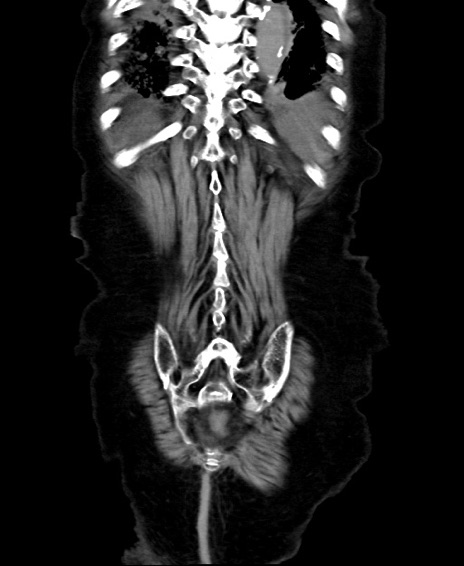

矢状断像